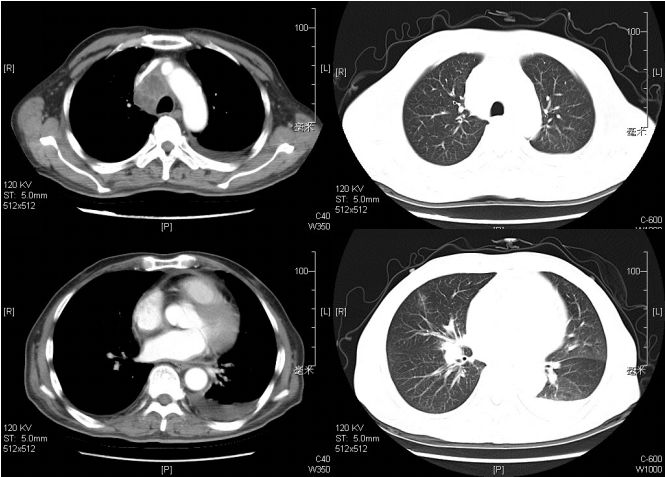

■ 胸部增强CT示:右肺门、纵膈内隆突下、气管前腔静脉后及胸廓入口处多发淋巴结增大,考虑淋巴瘤可能大,两侧少许胸腔积液,两肺下叶少许渗出,右肺中叶少许纤维灶(图1)。

图12015.12.1当地医院胸部增强CT(抗痨治疗前)

■ 2015-12-25复查胸部CT:纵隔内及右肺门多发肿大淋巴结,较前有所增大,右肺渗出,右肺中叶部分实变,右侧胸腔积液(图2)。

图2.2015.12.25当地医院胸部CT(抗痨治疗后纵隔淋巴结有增大)